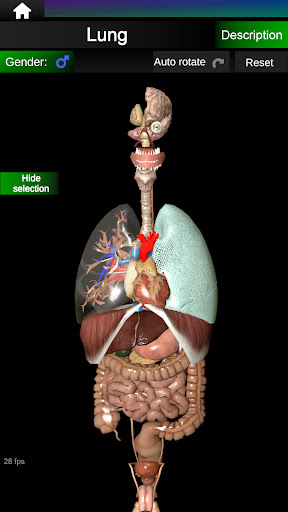

* Ademhalingssysteem, inclusief de luchtpijp, bronchiën, longen en een animatie van dit systeem.

* Hart, dat de atria, ventrikels, aorta en een animatie van dit orgel omvat.

* Gemakkelijk te openen en te navigeren (zoom, 3D-rotatie).

* Verberg of toon informatie.

* Vergelijk mannelijke en vrouwelijke organen.